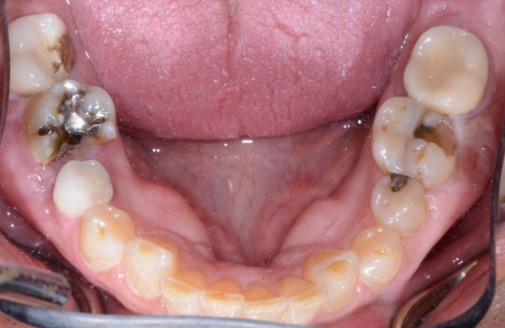

How many patients have you seen who continually break teeth? Some patients break multiple teeth within a short time frame, often, caused by cuspal interferences when the mandible is moving side to side or forward. Assess how many crowns a patient already has and ask them why the crowns were placed. Gather information from their past crown history to gain a respect for the system you’re about to put the next crown into. Every time we do a crown on a single fractured tooth, we’re placing our new crown right back into the system that broke it in the first place. Set a number in your mind of how many teeth a patient needs to break before we’re comfortable discussing balance.

Mobility

Often, patients recognize when they have a mobile tooth; the real challenge is catching mobility before it becomes noticeable to the patient. Here are some tips for doing so:

- Evaluate the stress on loose teeth.

- Check for fremitus.

- Have the patient place their finger on a premolar or incisor that has recession or wear, and see if the tooth moves.

- Check mobile teeth to see if those teeth are singlehandedly carrying the load in excursions.

- Evaluate periodontal status and bone support in the mobile tooth area and compare it to what you see throughout the mouth. A localized area of mobility with otherwise normal periodontal health can be an indicator of imbalance.

Tooth wear

Like pain, tooth wear can be multifactorial, but after a thorough history and clinical exam, we should be able to sort out tooth wear caused by extrinsic forces (acid erosion) vs. tooth wear caused by tooth-to-tooth contact (attrition).

Cases of attrition are often present in the unbalanced environment where a patient is naturally balancing themselves. The question here: What is the long-term consequence? Clinically, this can show anywhere from one canine with a flat incisal edge to an entire arch of teeth with completely flattened cusp tips. The worn area of one tooth or arch will have an equal and opposite pattern of wear in the other tooth or arch.